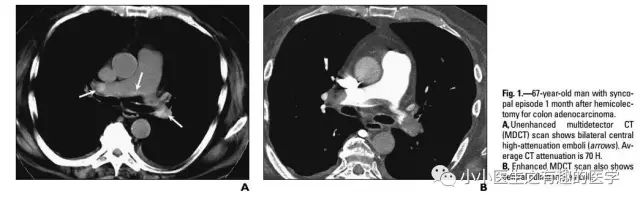

再介绍一位牛人:首都医科大学,附属北京友谊医院,放射科主任医师,李铁一教授。以前买过一本他的书。当时在读研究生,刚好有点钱,就买了,可惜书太老,图像不清楚,但书写得很好。

2004年,李铁一教授就说了:对于不能使用对比剂或因非典型心肺症状而仅作平扫的病例,肺动脉CT平扫的异常密度改变能提示急性肺动脉栓塞的存在。

文献五

国外有高手专门研究了CT平扫诊断肺栓塞的可靠程度。

高分辨CT平扫管腔内高密度征象诊断肺栓塞的敏感性36.0%, 特异性99.0%,阳性预测值90.0%,阴性预测值85.6% 。

高分辨CT平扫管腔内高密度征象诊断中心肺栓塞敏感性66.7%, 特异性99.1%。

4.李辉, 李铁一, 郝晓光. 值得关注的急性肺动脉栓塞平扫CT征象[J]. 中华放射学杂志, 2004, 38(11):1169-1172.

5.Tatco V R, Piedad H H. The validity of hyperdense lumen sign in non-contrast chest CT scans in the detection of pulmonary thromboembolism[J]. International Journal of Cardiovascular Imaging, 2011, 27(3):433-440.